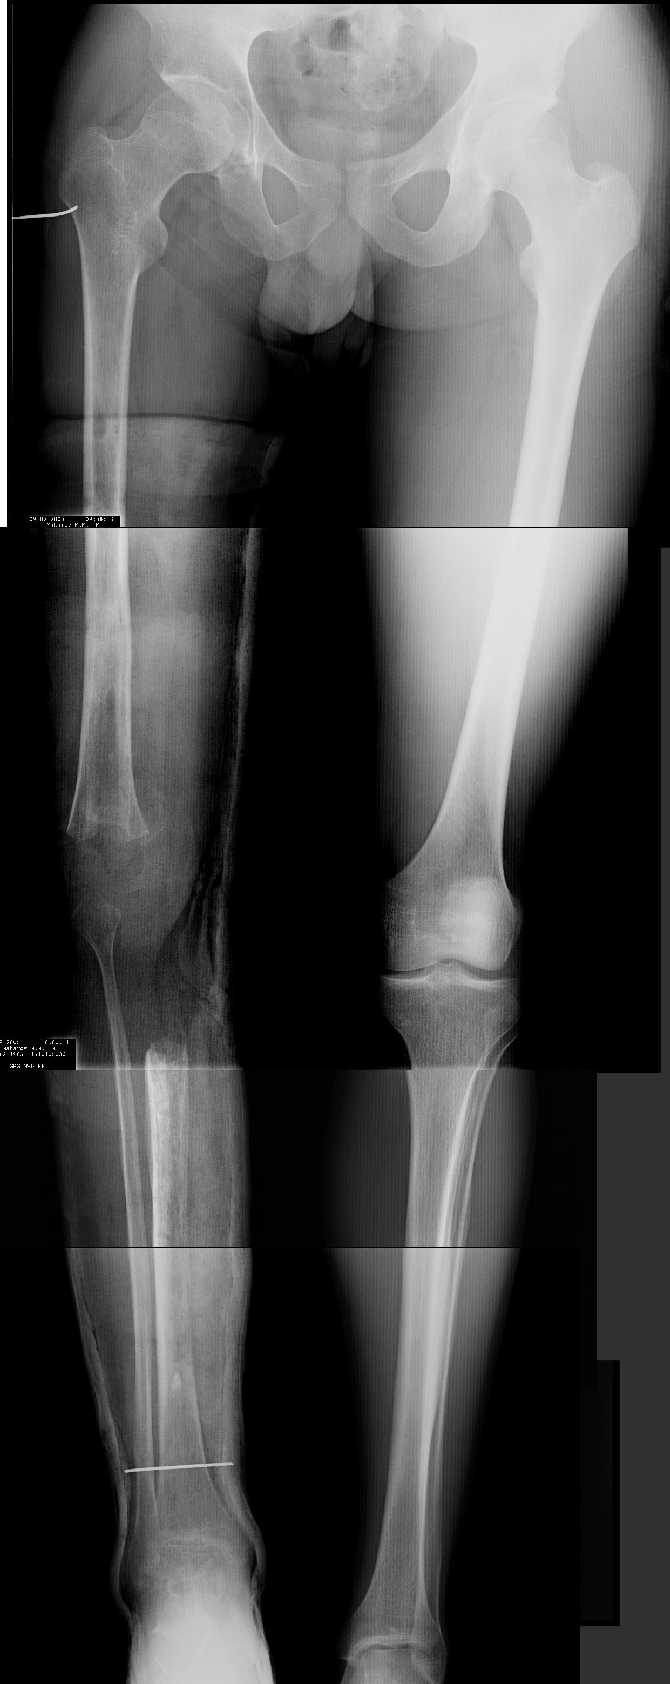

Прежде всего необходимо выполнить рентгенографию в таком положении, как это показано на рис.

После этого представится возможность оценить ось и сравнитьеё с нормой Рисунки из кники Dror Paley - Принципы коррекции деформаций. Этой теме посвящены 800 страниц. Хотя, учитывая контрактуру, это исследование не будет исчерпывающим.

AV> многооскольчатый перелом правой бедреннойљ кости на границе

AV> средней и нижней трети со смещением,

AV> В настоящее время стойкая разгибательная контрактура правого

AV> коленного сустава (сгибание 105-110 гр., разгибание 160-165 гр.),

AV> варусная деформация, болевой синдром.

имеется S-образная деформация бедра на фоне "многооскольчатого

перелома правой бедреннойљ кости на границе средней и нижней трети со смещением"

(хотя "длинные" снимки конечно же не помешали бы...)

На представленных снимках эта деформация как раз и не представлена.

1. Иллюстрации - во вложении.

Два бедра после эндопротезирования.

Авторы операции долго думали почему больная хромает.

Сдклали снимок - одна нога короче почти на 3 см.

Здоровый человек и то будет хромать.